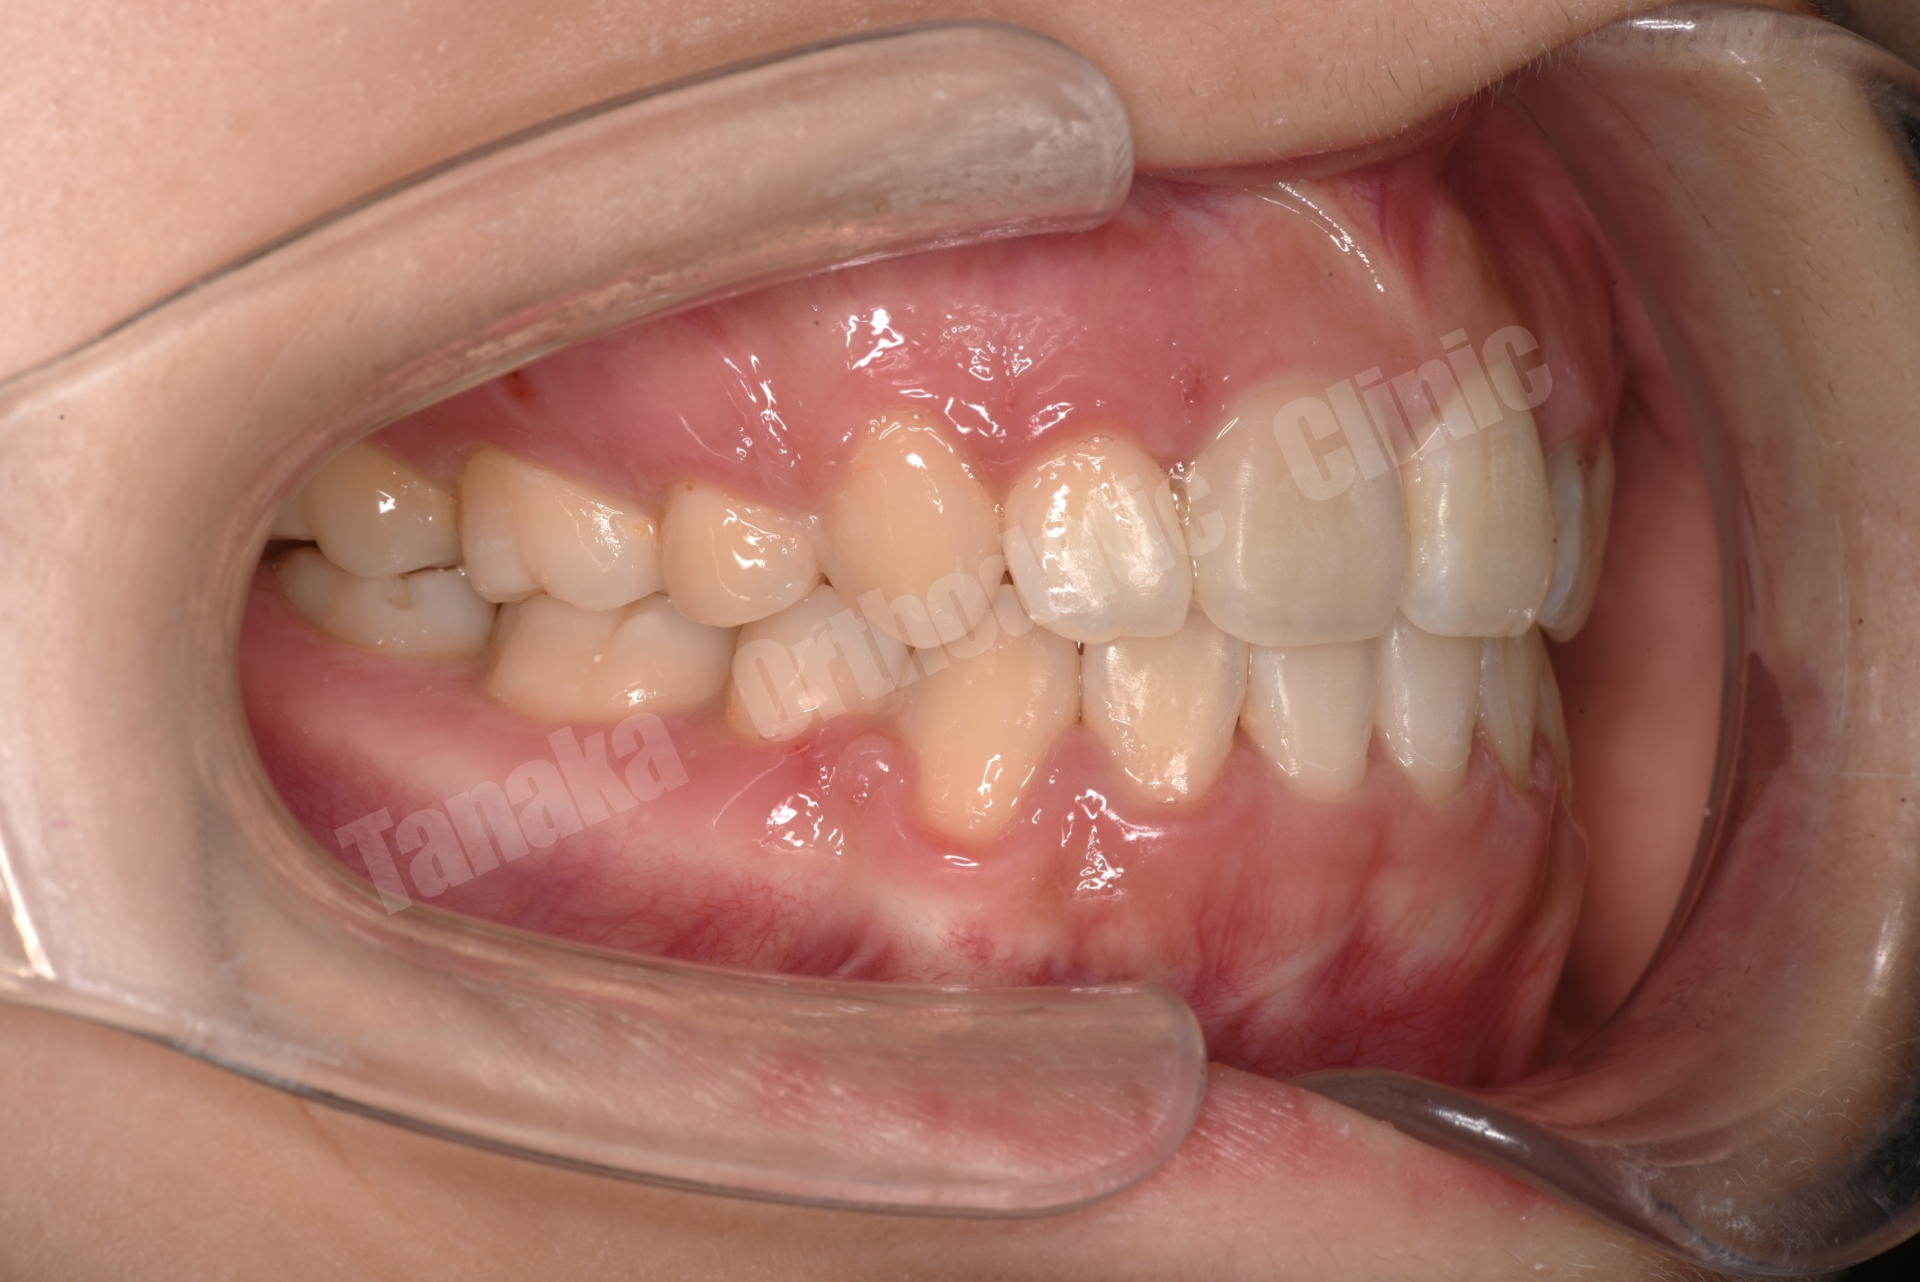

| 主訴 | 上下顎前歯のがたがた、口元が気になる |

| 年齢・性別 | 10代、女性 |

| 診断 | 上顎前突傾向(下顎骨の後方位)、上下顎歯列の叢生、上下左右8番を認める |

Angle Class I(第一大臼歯の正常なかみ合わせ)

ハイアングル傾向(下顎骨が後下方へ回転するタイプ)

上下前歯部に叢生(がたがた歯列)

下顎前歯(L1)が前方に傾く「唇側傾斜」